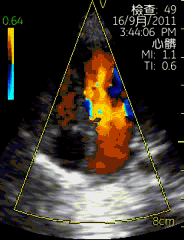

vscan临床图片 心脏